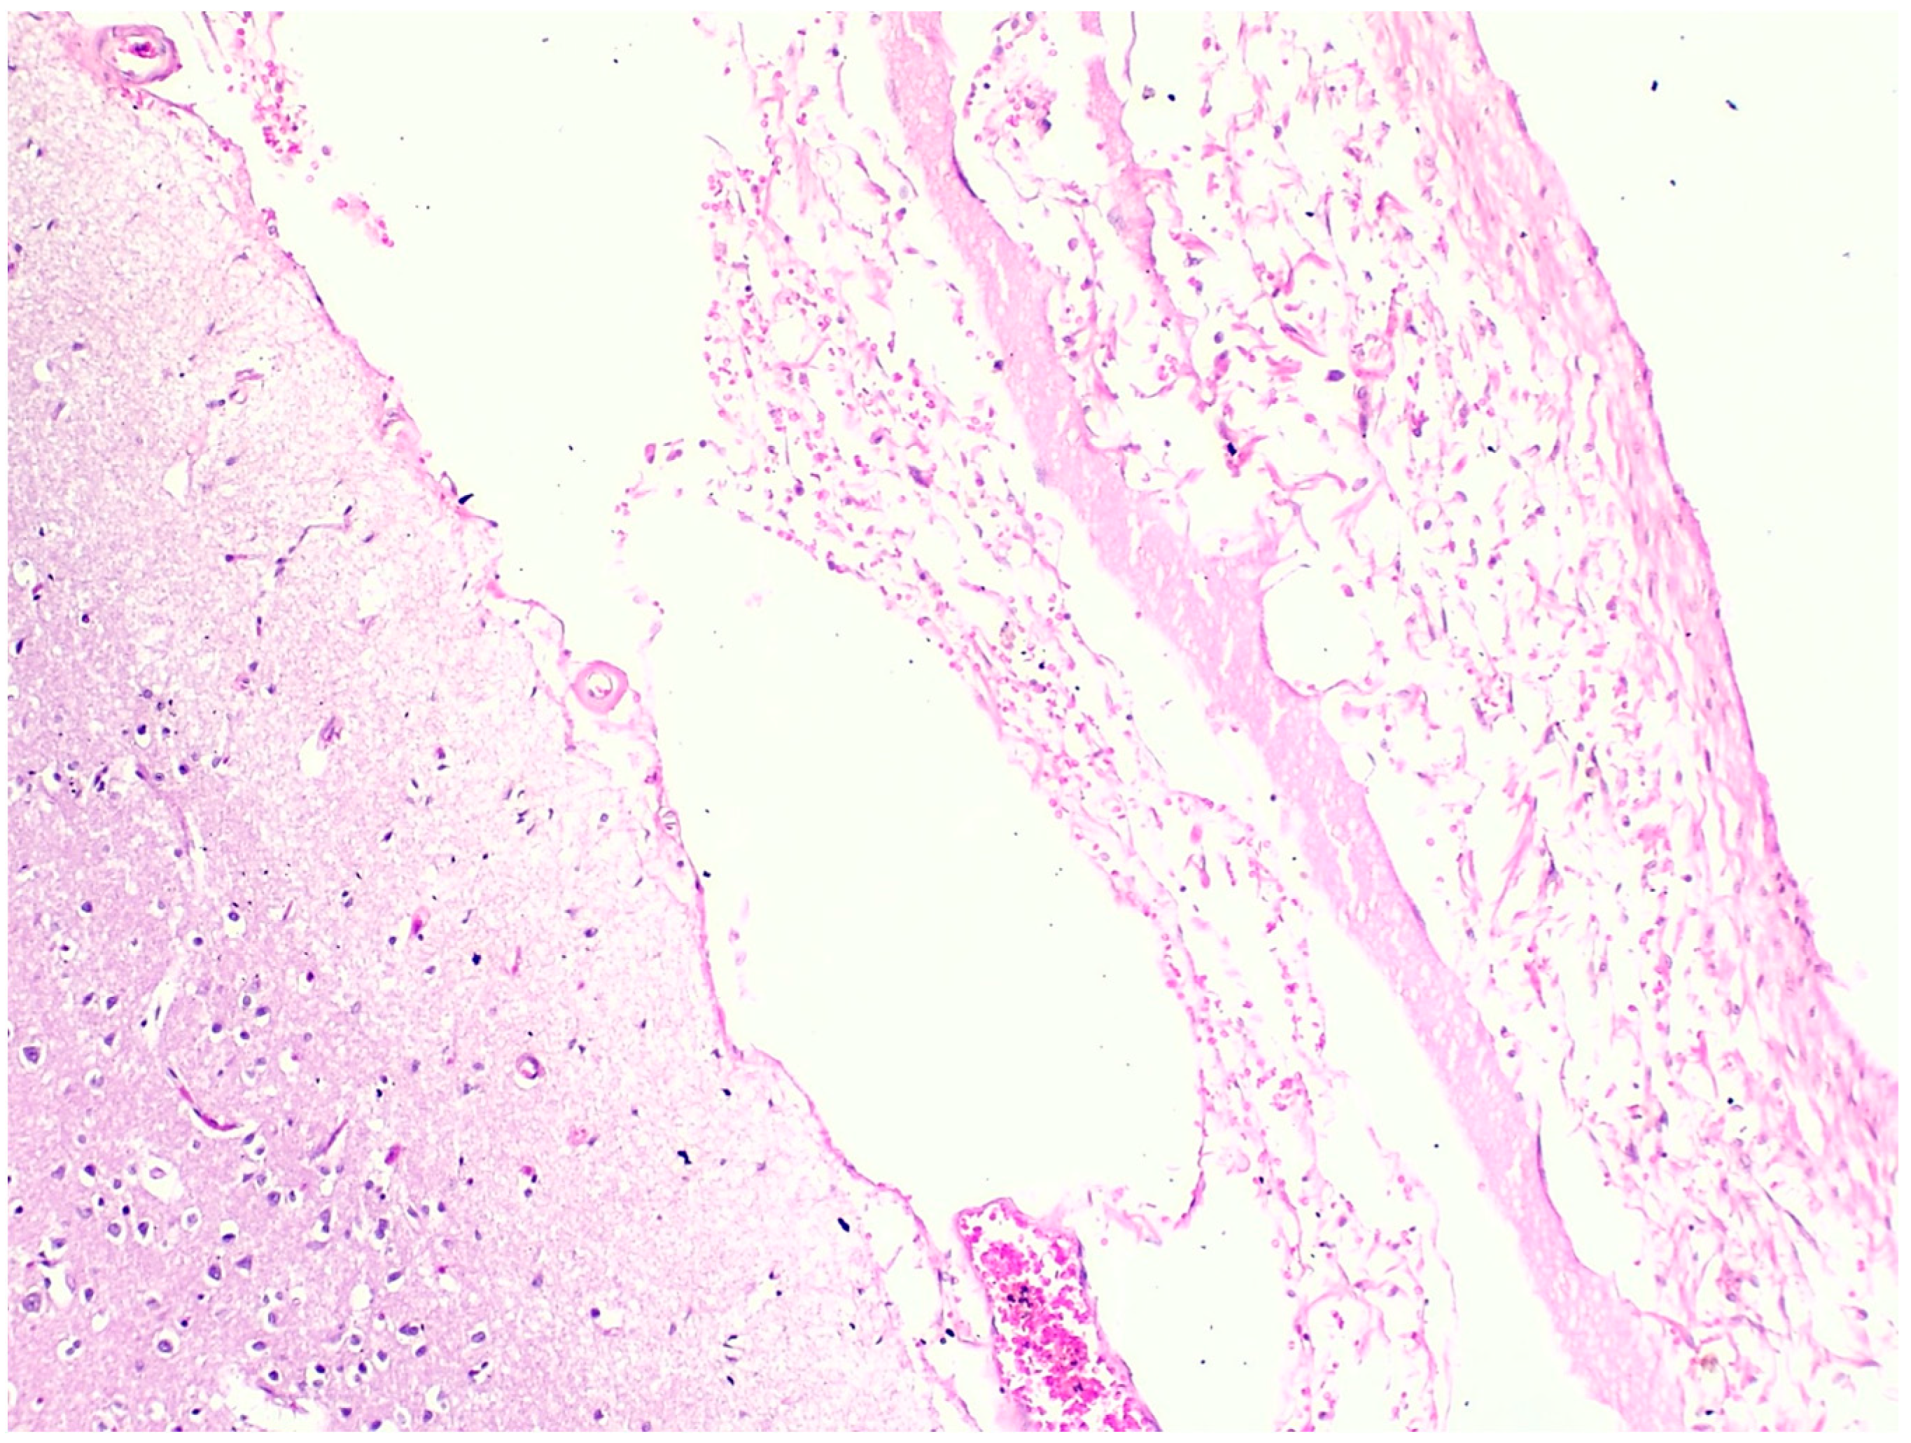

3.2. Microscopic Histopathological Findings

| Autopsy Case No. | Brain | Heart | Lung | Liver | Spleen | Kidney | Adrenal Gland | Esophagus/ Stomach |

|---|---|---|---|---|---|---|---|---|

| 1 | N/A | Hemorrhage at subendocardial and myocardium | Edema | Steatosis | N/A | Partial autolysis | Partial autolysis | N/A |

| 2 | N/A | N/A | N/A | Steatosis | N/A | N/A | N/A | N/A |

| 3 | Subarachnoid congestion, hemorrhage, eosinophilic neurons | Thrombosis, myocardial necrosis, focal subendocardial hemorrhage, atherosclerosis | Diffuse alveolar damage, fibrin platelet thrombi | Multifocal ballooning degeneration (hepatocyte), steatosis | Congestion | Acute tubular necrosis, fibrin platelet thrombi in glomeruli | Focal cortical necrosis | Mucosal infarct, hemorrhage |

| 4 | N/A | N/A | Edema, congestion, petechial hemorrhage | Steatosis | Congestion | N/A | N/A | Mucosal hemorrhage, esophagitis |

| 5 | N/A | Atherosclerosis | Diffuse alveolar damage, hemorrhage, fibrosis | Cholestasis | N/A | Acute kidney injury | N/A | N/A |

| 6 | N/A | Myocardial infarction, coronary occlusion | Edema, congestion, petechial hemorrhage | N/A | N/A | N/A | Lipid depletion | Mucosal infarct, hemorrhage |

| 7 | Red blood cells within the subarachnoid space | Cardiomegaly, hemorrhage at myocardium | Edema, congestion, | Steatosis | Congestion | N/A | Lipid depletion of cortical cells | Superficial mucosal hemorrhage |